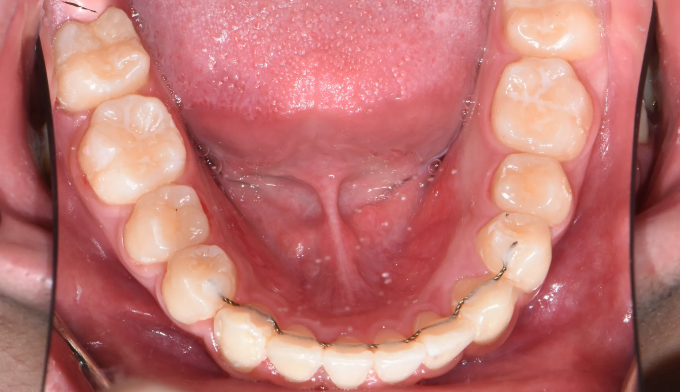

상악확장장치를 통해 악궁을 넓혀주고 치아를 배열해줍니다.

치료기간은 15개월 소요되었습니다.